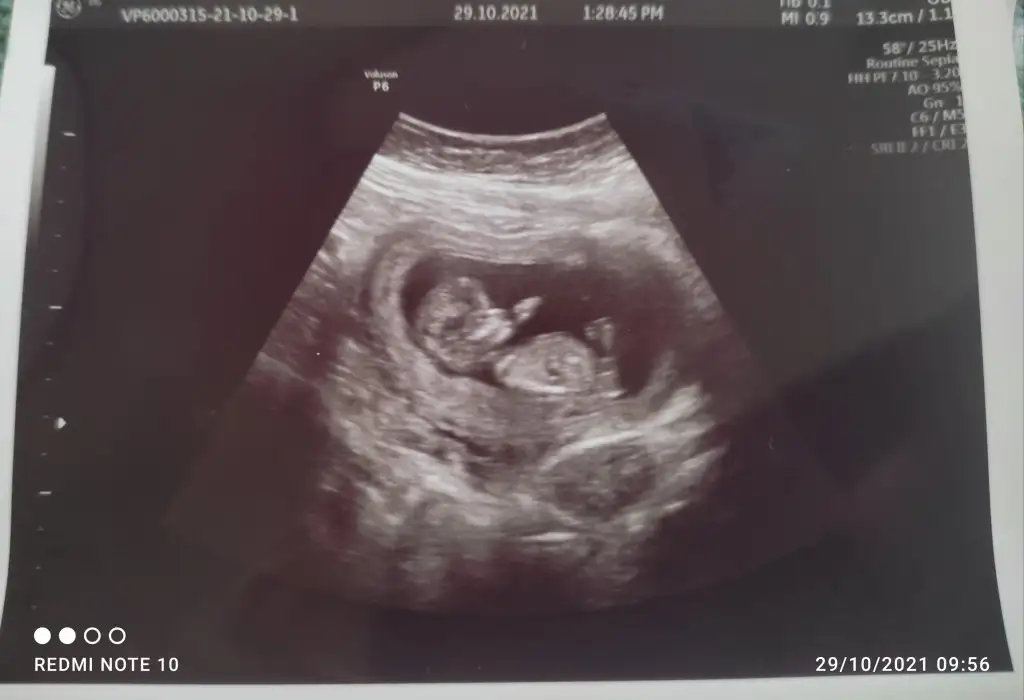

Erkek gibi sankiIkra meyra Eki Görüntüle 2941942 bende bir tahmin rica edebilir miyim

12+4 Dr bir tahmin yürütmedi çok merak ediyorumEki Görüntüle 2941943

Erkek gibi